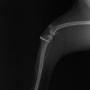

■ 症例20 ポメラニアン 8ヶ月 1.8kg

左右膝蓋骨脱臼 グレードⅢ

2ヶ月前から間欠的跛行が認められ、両膝の膝蓋骨脱臼整復術を行った。

手技は縫工筋及び内側広筋の解放、脛骨粗面の外側転位、滑車ブロック形造溝術、内外側関節包の縫縮を選択し実施した。

右側の膝蓋骨脱臼は上記手技で整復されたものの、左側はそれのみでは膝蓋骨が浮く様子が認められた。その為、PDS縫合糸にて膝蓋靱帯を1糸のみ縫合し、靱帯の縫縮を行った。

膝蓋骨脱臼は膝関節における膝蓋骨の内外側の脱臼と定義されるが、時として単純な内外の脱臼ではなく、膝蓋骨が大きく前方に浮き上がるように脱臼する場合がある。特にトイプードルやポメラニアンといった犬種に多く認められる。

内側脱臼に加えて前方への浮き上がりを矯正する為に、従来より脛骨粗面転移により膝蓋靭帯を外方と下方に引っ張り、固定する方法を選択する。膝蓋骨の前方への浮き上がりが軽度の場合は、従来法ではなく関節包の縫縮で対応していた。しかし、一部の症例で膝蓋骨の動きが悪くなり伸展機構が円滑に機能せずロボット様歩行になるケースがあった。

その為、膝蓋靭帯自体を縫縮する方法を採用した。この方法により、膝関節の伸展機構を妨げず膝蓋骨の軽度の浮きを矯正することが可能となった。

本症例の経過は良好である